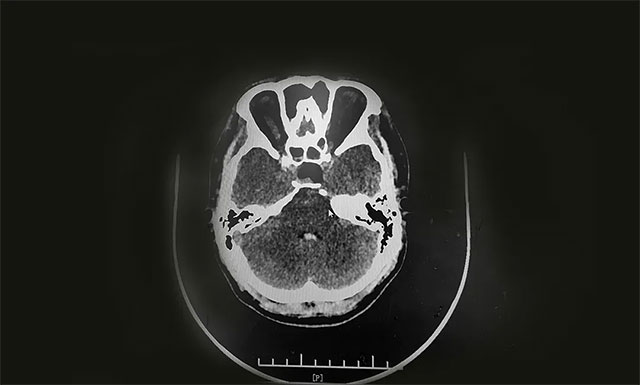

術(shù)中,在蔡司顯微鏡(雙熒光)下,見(jiàn)黃白色腫物,質(zhì)韌,其外有包膜覆蓋。李士其教授在充分保護(hù)好海綿竇、頸內(nèi)動(dòng)脈、視神經(jīng)等結(jié)構(gòu)前提下,將鞍內(nèi)可見(jiàn)腫瘤順利切除,腫瘤大小約2.5cm*1.5cm*1.5cm,并留取腫瘤送檢病理。手術(shù)順利完成,術(shù)中只失血約20毫升。

目前,莉莉正在恢復(fù)中,經(jīng)過(guò)檢查其體內(nèi)泌乳素、生長(zhǎng)激素正逐步恢復(fù)正常。李士其教授叮囑其出院后要做好定期復(fù)查。

▲ 術(shù)后CT顯示腫瘤被切除